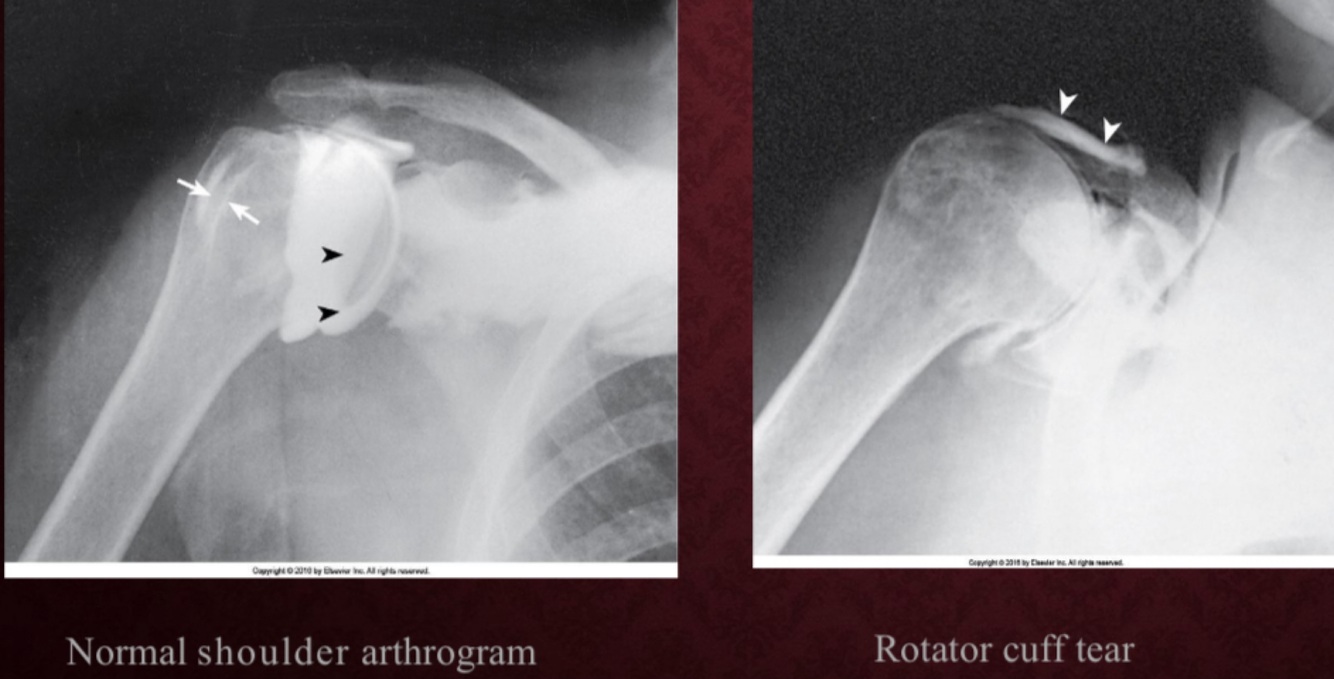

SHOULDER ARTHROGRAM

-10 to 12 mL contrast injected

-Common Shoulder Projections:

-AP internal and external rotation

-30 degree oblique

-Axillary

-Tangential

Shoulder arthrography is performed primarily for the evaluation of

partial or complete tears in the rotator cuff or glenoid labrum, persistent pain or weakness, and frozen shoulder